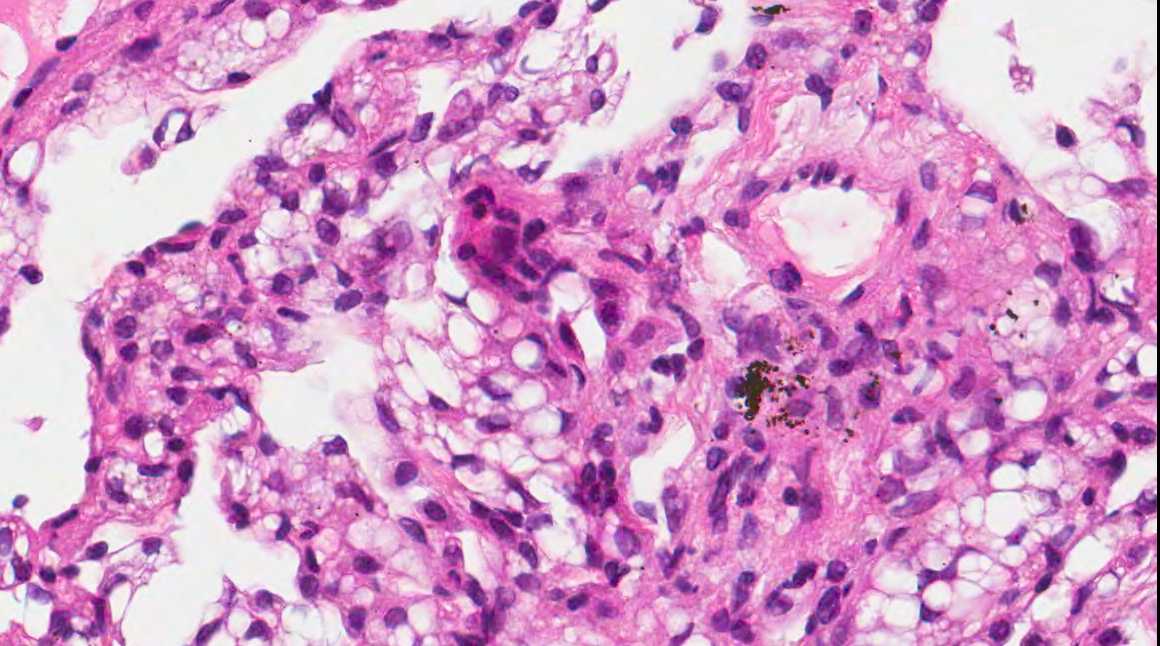

A 71 year old man with recent history of meningitis presented with recurrent episodes of pneumonia. High resolution CT scans showed crazy paving and tree in bud images. The patient underwent a transbronchial biopsy.

Micro images:

Diagnosis: Aspiration with granulomatous bronchiolitis and lipoid pneumonia

Aspiration of particulate matter, traditionally observed at autopsy, has also been described in debilitated patients, who often have a history of recurrent pneumonia, which is often unrecognized (Am J Surg Pathol 2007;31:752, Am J Surg Pathol 2010;34:1456). It usually (88%) shows bronchiolitis obliterans organizing pneumonia, often with multinucleated giant cells, acute bronchopneumonia / bronchiolitis or suppurative granulomas. Foreign material is usually but not always present (Am J Surg Pathol 2011;35:426).

The differential diagnosis of pulmonary granulomatous inflammation is broad and requires special stains, culture and clinical correlation (Ann Diagn Pathol 2003;7:127, Histopathology 2007;50:289).

Lipoid pneumonia is often an incidental postmortem finding associated with debilitating disease. The lipid may be exogenous (from nasal sprays or inhalation of other lipid containing substances) or endogenous (bronchial obstruction).

A 71 year old man with recent history of meningitis presented with recurrent episodes of pneumonia. High resolution CT scans showed crazy paving and tree in bud images. The patient underwent a transbronchial biopsy.

Micro images:

Diagnosis: Aspiration with granulomatous bronchiolitis and lipoid pneumonia

Aspiration of particulate matter, traditionally observed at autopsy, has also been described in debilitated patients, who often have a history of recurrent pneumonia, which is often unrecognized (Am J Surg Pathol 2007;31:752, Am J Surg Pathol 2010;34:1456). It usually (88%) shows bronchiolitis obliterans organizing pneumonia, often with multinucleated giant cells, acute bronchopneumonia / bronchiolitis or suppurative granulomas. Foreign material is usually but not always present (Am J Surg Pathol 2011;35:426).

The differential diagnosis of pulmonary granulomatous inflammation is broad and requires special stains, culture and clinical correlation (Ann Diagn Pathol 2003;7:127, Histopathology 2007;50:289).

Lipoid pneumonia is often an incidental postmortem finding associated with debilitating disease. The lipid may be exogenous (from nasal sprays or inhalation of other lipid containing substances) or endogenous (bronchial obstruction).